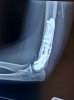

On this X-ray you can see the plates.

upload_2022-11-28_16-41-43.jpeg